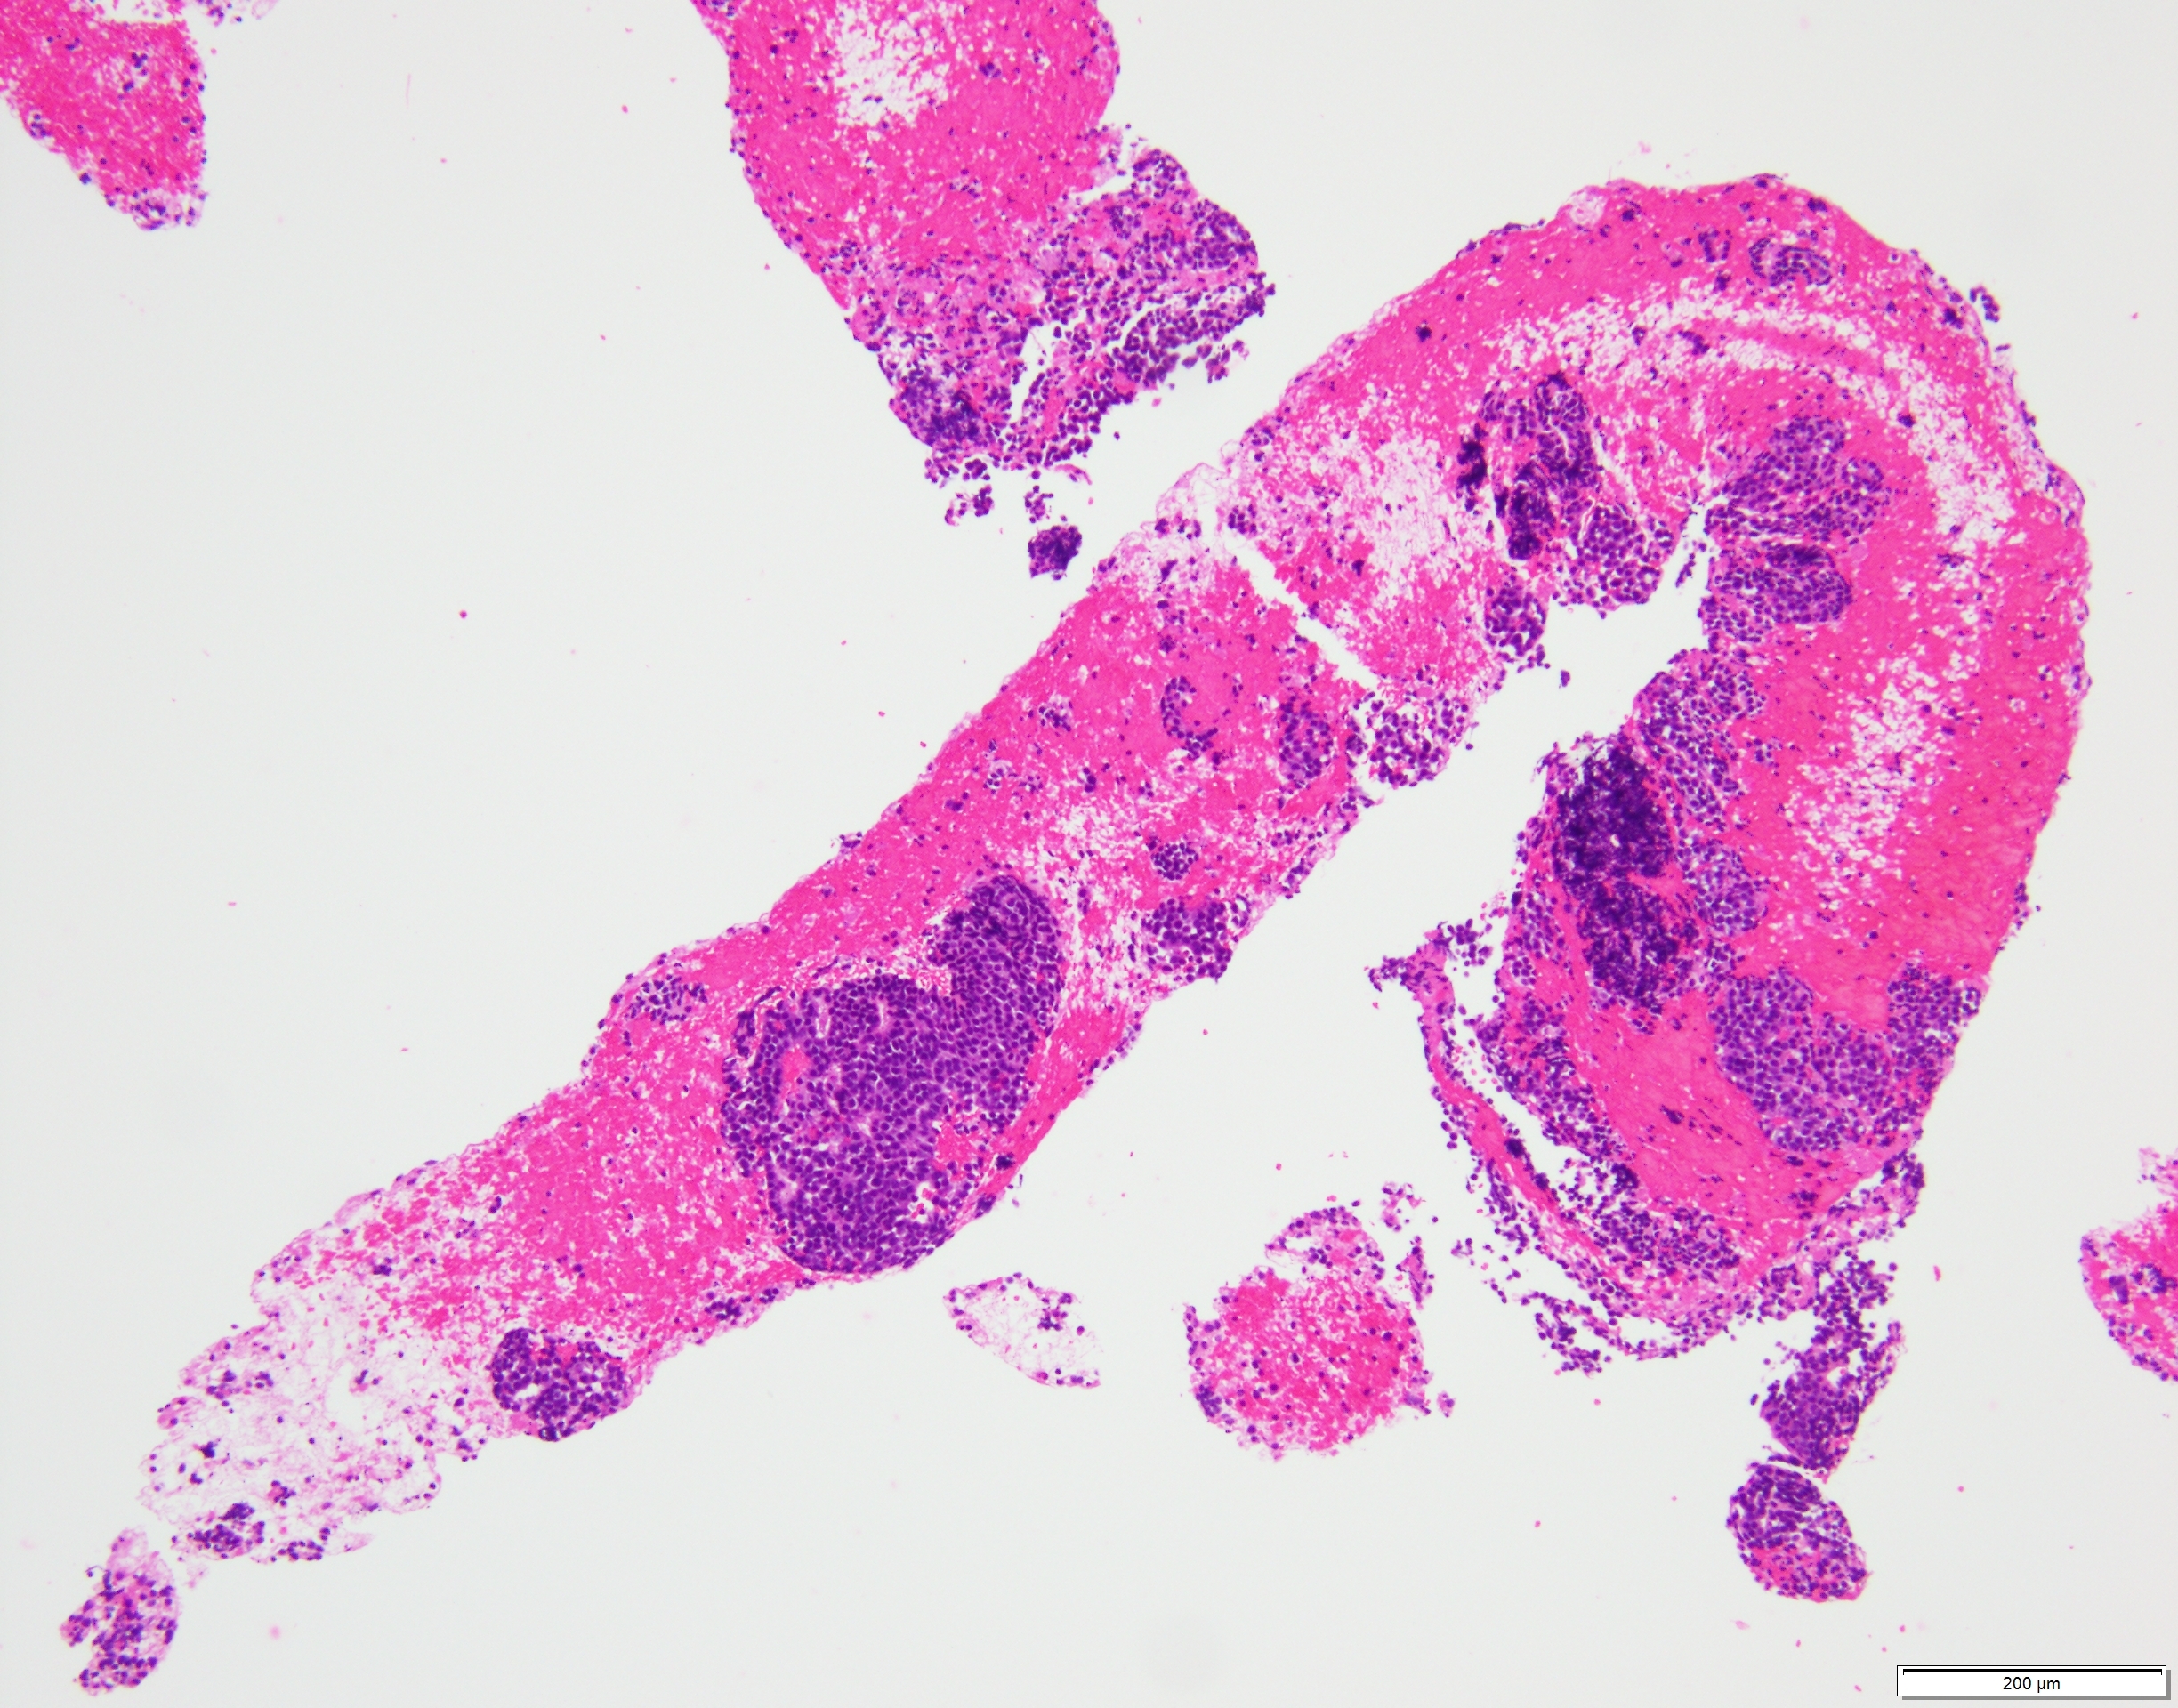

比較的小型で類円形核を有するN/C比の高い細胞が集簇性〜孤立性に多数認められた。

出現している異型細胞は一様で核線の形成やロゼット様の構造を認め、NETを推定した。

組織でも同様の異型細胞を認め、クロモグラニン陽性、MIB-1 LI 15%、ER陰性、GATA3陰性を呈し、NET G2と診断された。

HE×10 HE×20 HE×40 クロモグラニン×40